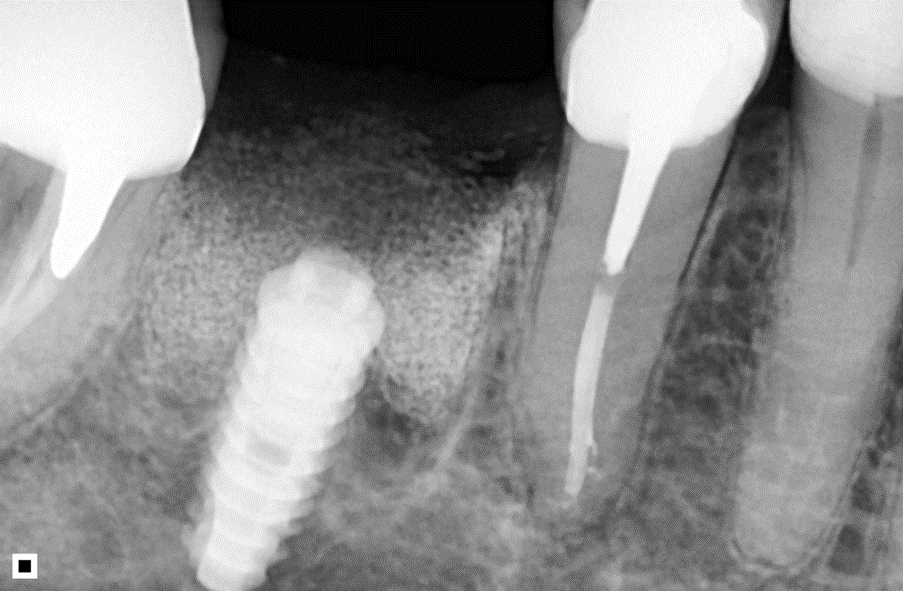

O Extra Graft é um biomaterial muito interessante para aplicação nestes casos, pois apresenta-se na forma de blocos fracionados (0,5g / 1g / 2g) e tem em sua composição 75% de hidroxiapatita (principal componente mineral do osso) e 25% de colágeno do tipo I (proteína mais abundante na porção orgânica do osso) – ambos de origem bovina. Devido a essa composição, possui grande atividade osteocondutora e maior adesão dos osteoblastos, aumentando a velocidade de neoformação óssea. Além disso, a porção de colágeno gera maior estabilidade do coágulo e ação hemostática, promovendo menor sangramento pós operatório e maior conforto ao paciente. O Extra Grafté de fácil manuseio e condensação dentro dos alvéolos e é radiopaco, facilitando a conferência do preenchimento via radiografia final do procedimento.

A sequência de imagens a seguir apresenta casos da aplicação clínica do Extra Graft em cirurgias de exodontia e implante imediato com preenchimento dos gaps, e apenas exodontia e preenchimento alveolar para favorecer a regeneração óssea.